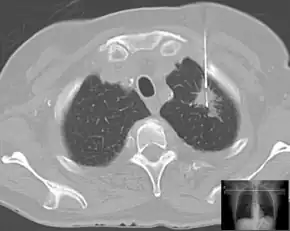

Lung | Biopsies of the lung can be performed in a variety of ways depending on the location. |